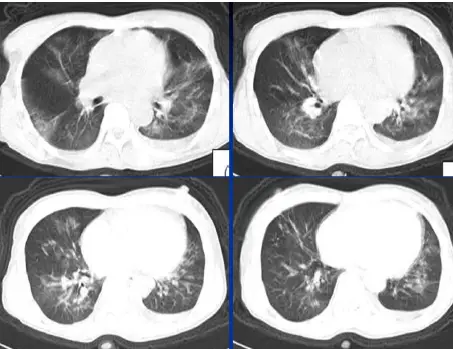

病例:男,33岁,急性肾衰肺水肿。CT表现:①肺间质性肺水肿:两肺血管束增多、增粗,边缘模糊;②肺泡性肺水肿:两肺透光度减低,并见广泛性分布结节样、斑片样密度增高影及毛玻璃样影,边缘模糊,以两肺内、中带分布较明显,形成典型“蝶翼征”;③胸腔积液。